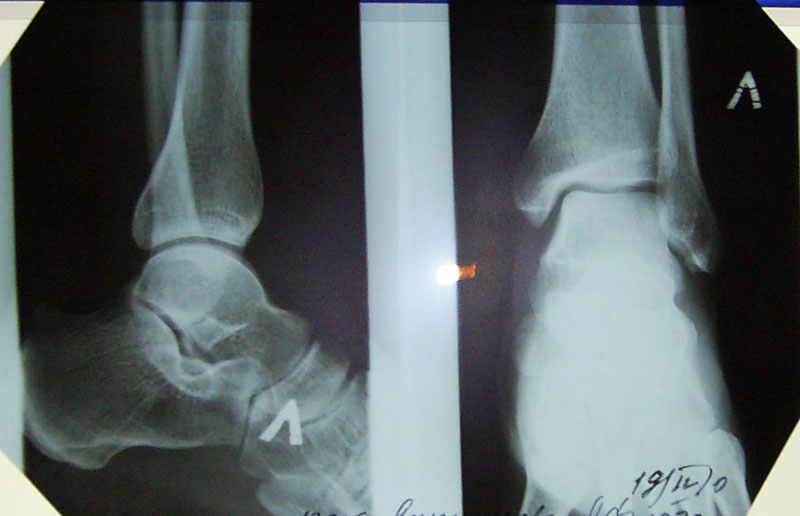

Застарелый краевой перелом

Добрый день, подскажите пожалуйста у меня опухает наружная ладыжка в течении 1,5 года.

Пошла к хирургу меня отправили на рентген. Обнаружили застарелый краевой перелом. В следствии чего он мне доставляет боль.Врач предлагает сделать операцию по удалению обломаного фрагмента или оставить все как есть, говорит ничего страшного нет, подскажите пожалуйста стоит делать операцию? Заранее спасибо.